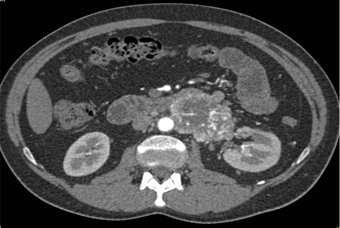

In this mildly hypertensive patient the best diagnosis is?

CTisus Quiz   CTisus Quiz